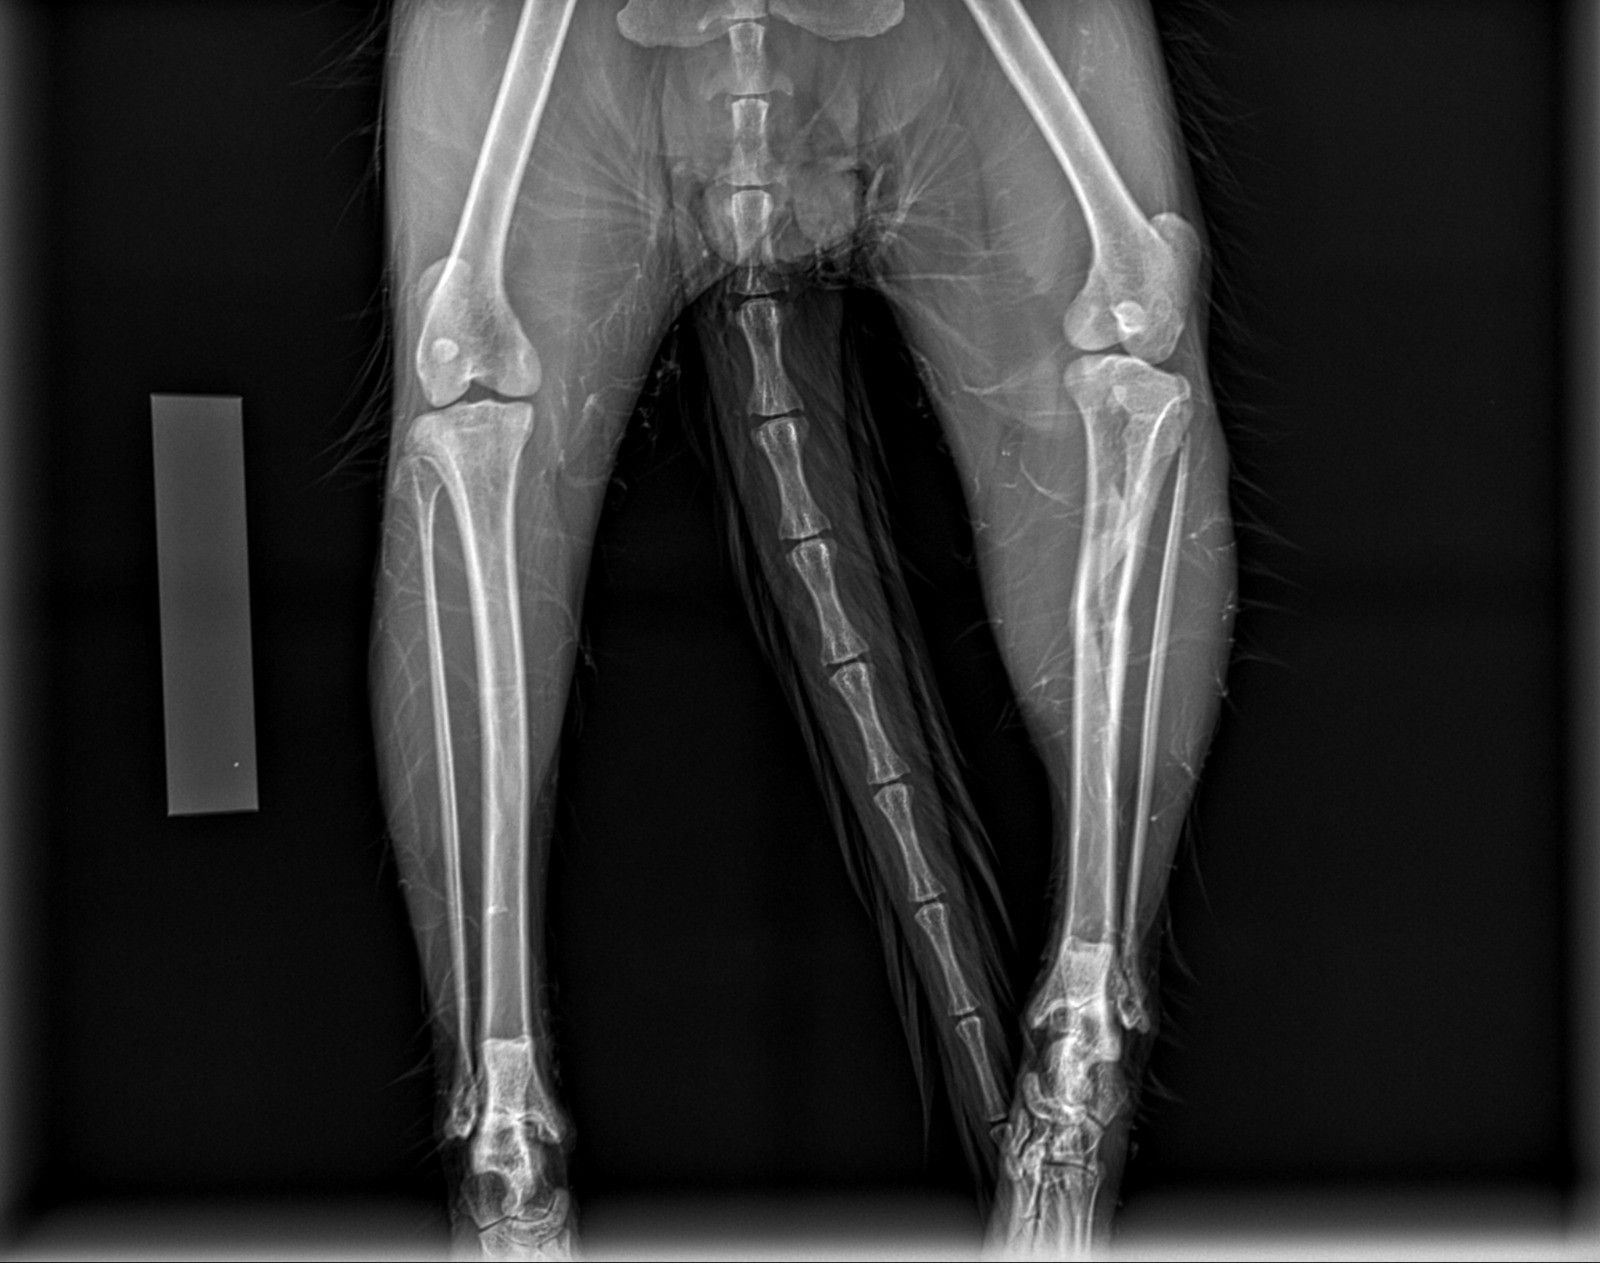

Per offrire cure sempre più efficaci e sicure, la struttura si avvale di tecnologie di ultima generazione. Un nuovo apparecchio radiografico digitale diretto consente diagnosi rapide e dettagliate, migliorando l’accuratezza delle valutazioni cliniche. Inoltre, la collaborazione con un chirurgo esperto e l’impiego di strumentazione chirurgica all’avanguardia permettono di eseguire interventi con maggiore precisione, sicurezza e rapidità. Tra questi, la sterilizzazione e altre procedure chirurgiche risultano notevolmente agevolate, garantendo il massimo benessere per il paziente e un recupero più rapido.